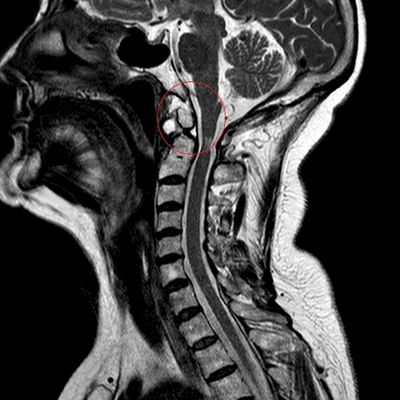

МРТ шейного отдела позвоночника. Стеноз позвоночного канала . Сагиттальная Т2-взвешенная МРТ.

МРТ: перелом зубовидного отростка второго шейного позвонка (сагиттальная плоскость, Т2 ВИ)